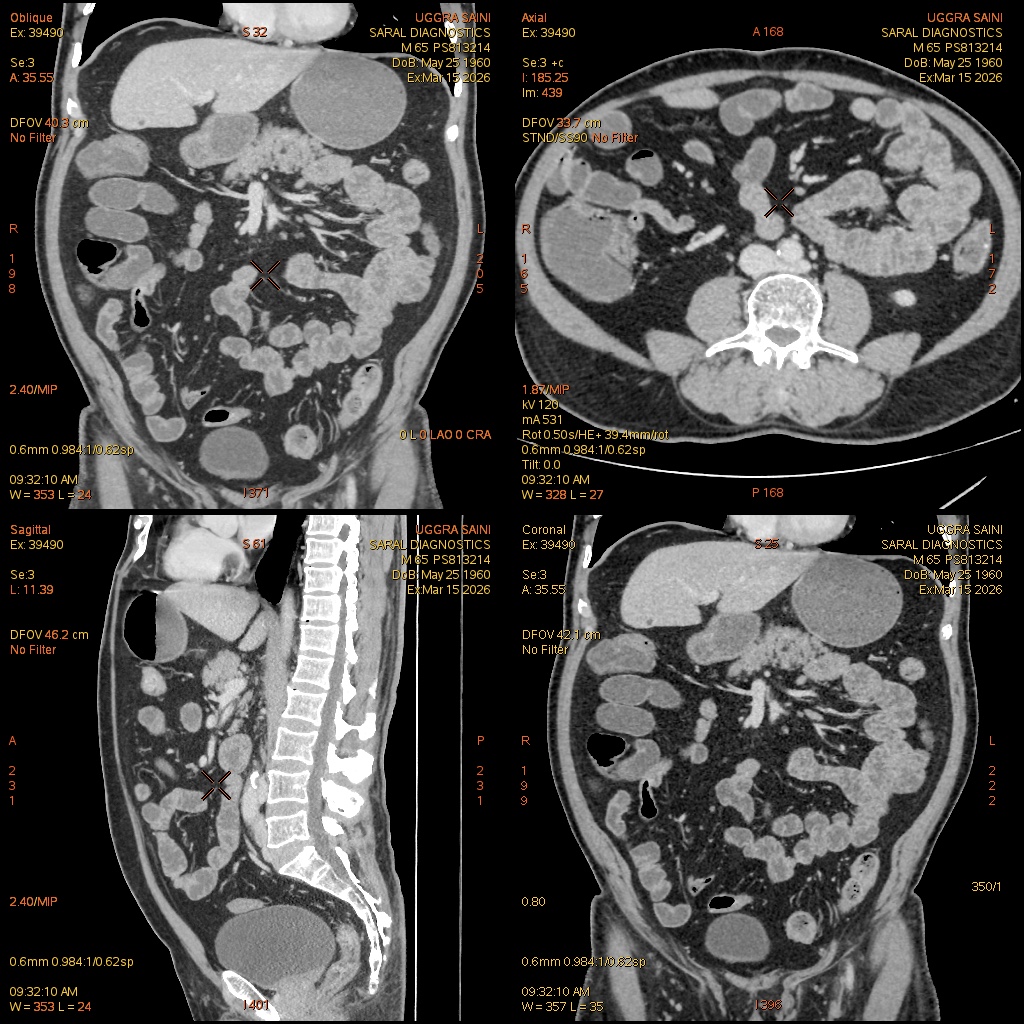

Reference Image

Enterography (Scan Charges Only)